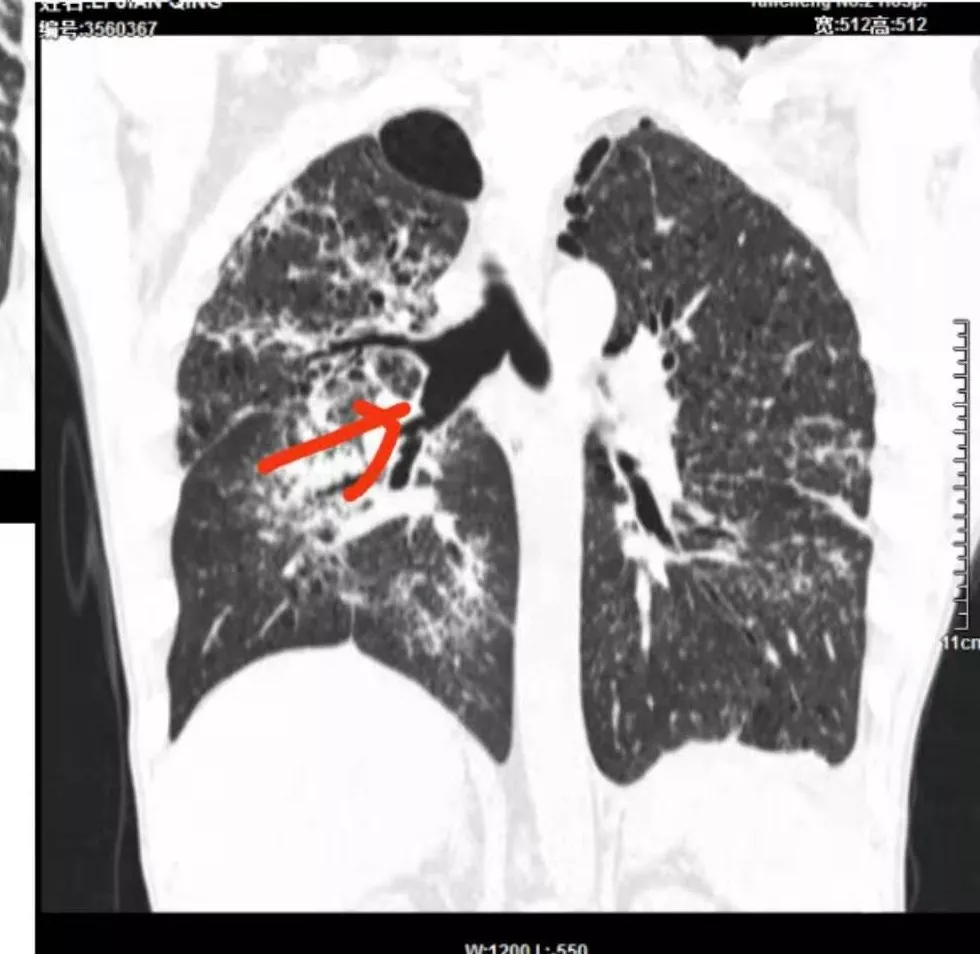

间质性肺结核是结核的一种特殊影像学表现,为继发性肺结核,影像学表现与常见的继发性肺结核有所不同,有一定的特征性:

病灶呈片状磨玻璃密度影,呈典型的烟花征。磨玻璃影密度偏高,有网结节样改变,与正常肺实质分界清楚,且常见相对高密度的勾画。

烟花征分为3肿类型:晕征、反晕征及均匀分布。

病变一般沿血管支气管束分布或小叶分布,一般上肺多于下肺(这与常见继发性肺结核分布相若)。

常会伴有其他继发性肺结核病灶,如斑片影、结节影,树芽征,新旧不等改变。

2. 肺气肿背景(小叶中心性肺气肿);双肺多发病灶整体沿血管支气管束及胸膜下分布,以上叶及下叶背段分布为主,有实变及GGO,边界清楚,有树芽,小叶间隔及中央间质增厚,叶间裂见到多发结节,部分支气管不规则牵拉扩张,提示病灶纤维化明显,结合临床病史,考虑病灶为间质性感染,肺门及纵隔内有钙化淋巴结,小叶间隔结节,考虑淋巴道增值性疾病可能,综合常规要怀疑间质性肺结核。